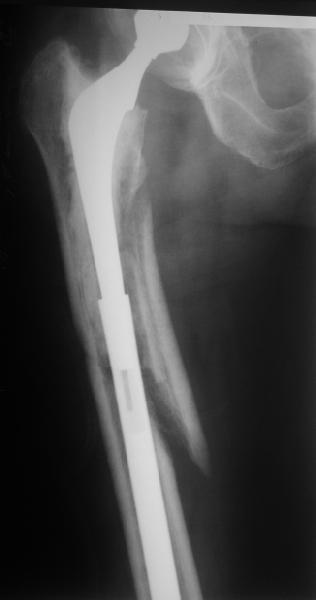

Hello! This is just illustration in one of the choice of treatment

Michael